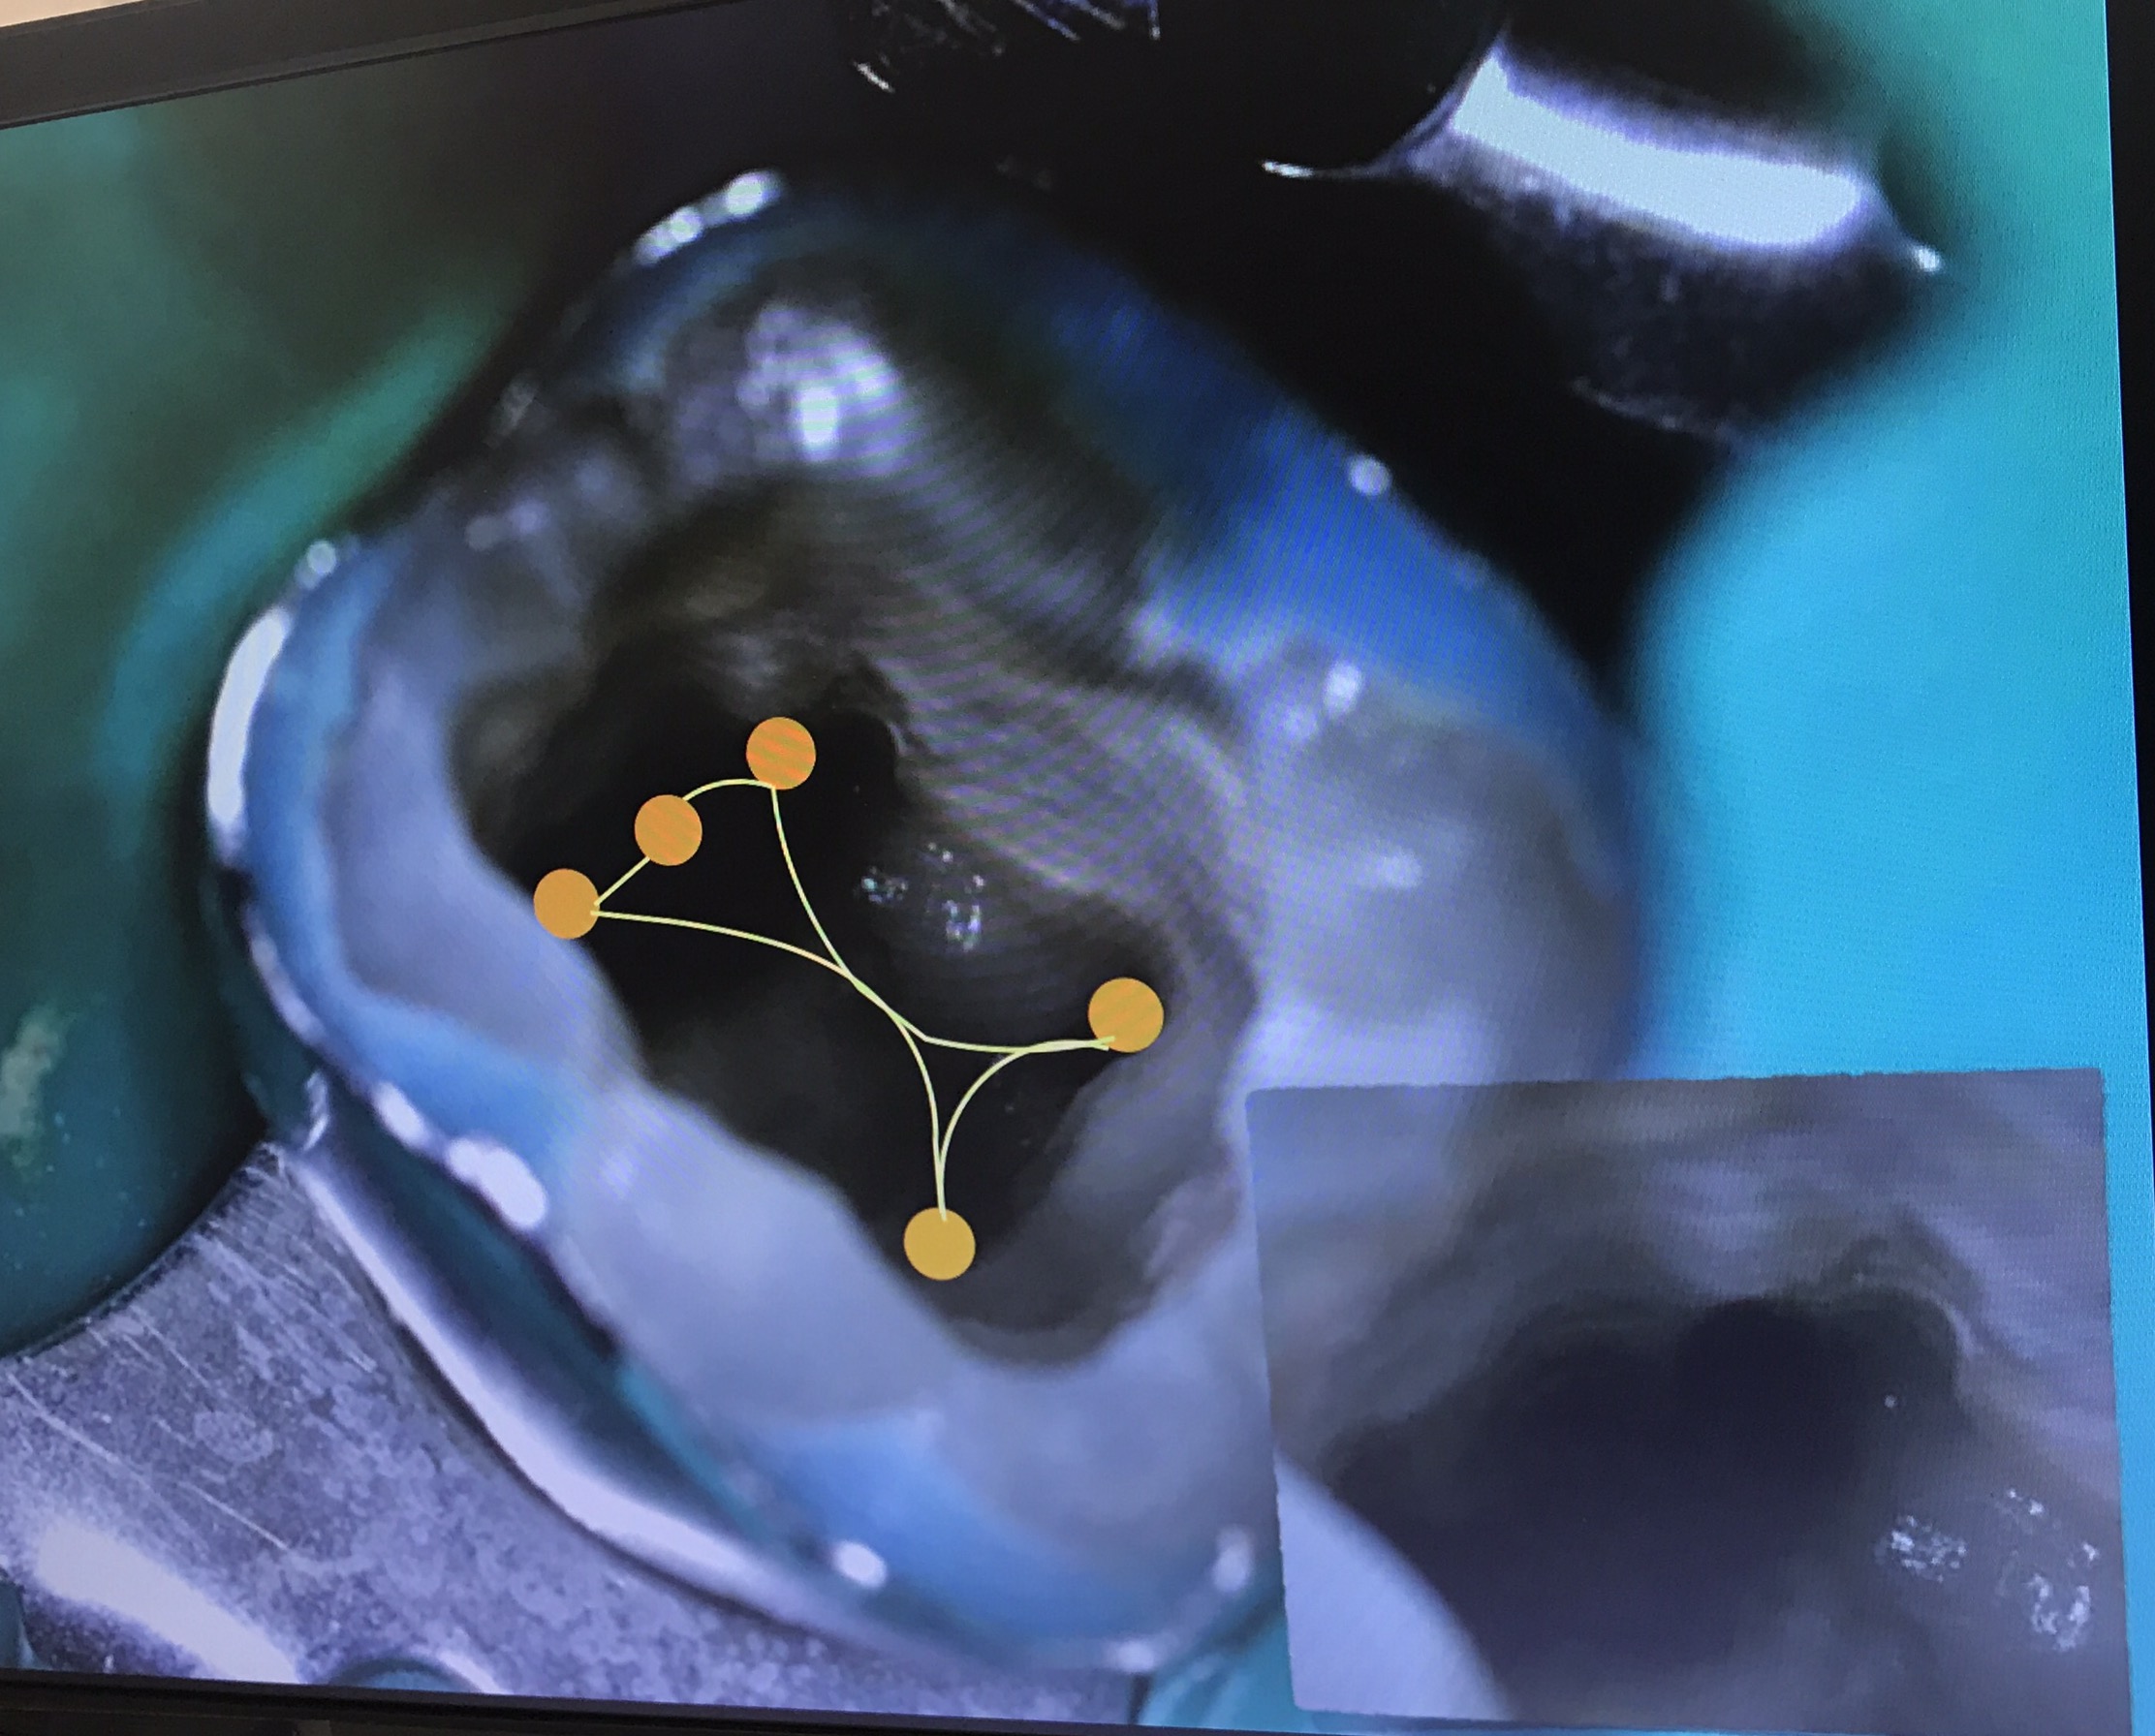

อันนี้คือ case จริงครับ ส่วนที่ Outline ไว้ตรงกลางคือ รอย Perforate

จุดสีเหลือง คือ canal ที่ถูกต้อง

วงกลมสีแดง แสดงส่วนที่ถูก repair ด้วย MTA